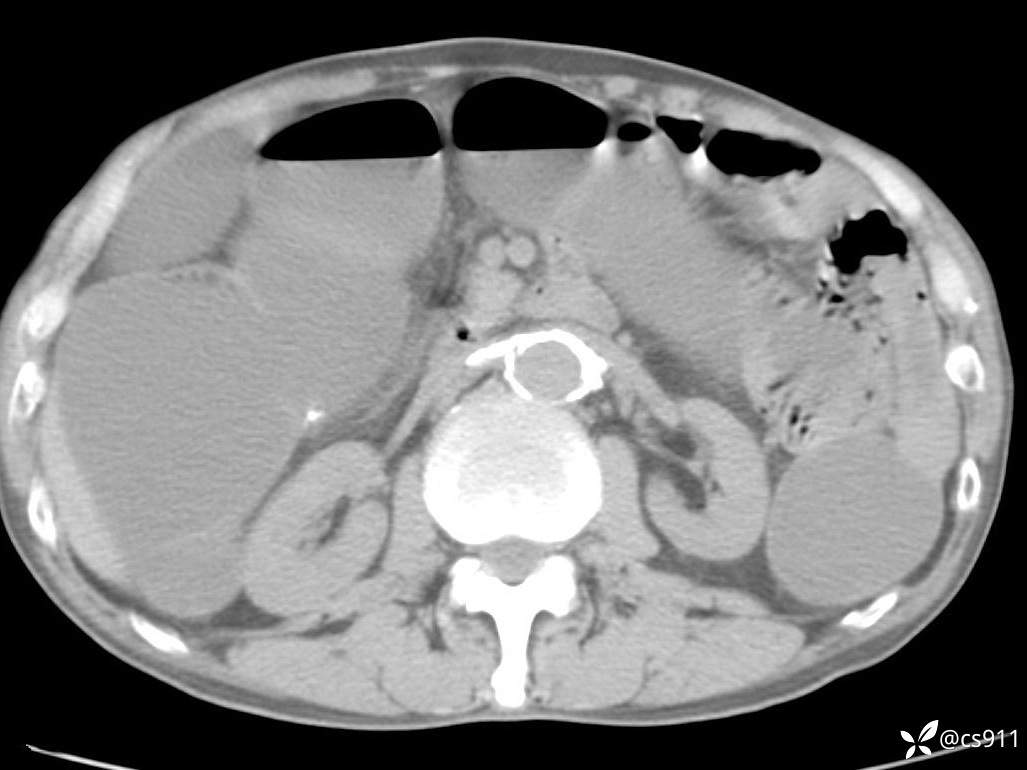

急腹症之急诊CT,原因?答案公布

男,77岁,腹痛、腹胀伴恶心呕吐1天。呕吐胃内容物,非喷射性呕吐,有咖啡色样胃内容物,诉有胃穿孔病史。查体:全腹平,下腹部压痛,全腹无反跳痛,叩诊呈浊音,移动性浊音阴性,肠鸣音减弱,1-2次/分。肛检:直肠未扪及明显肿物,可触及大量粪块。

血淀粉酶(AMY) HH 1859 U/L 35-135